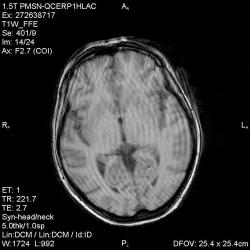

Из анамнеза - Женщина 45 лет. За год похудела на 15 кг (со слов матери), в последние месяцы случались эпизоды потери сознания. Онкозаболеваний и прочая в анамнезе нет. Сознание спутанное, из особенностей в анализах только подъем амилазы крови.

"Раскрою" карты. Мы подумали о синдроме MELAS (mitochondrial encephalomyopathy, lactic acidosis and stroke) - дословно, митохондриальная энцефаломиелопатия, лактоацидоз и инсульт. В качестве дифференциальной диагностики можно было бы предположить вирусный энцефалит, но опять-таки, расположение очагов смущает - только с одной стороны и в абсолютно различных структурах.

В данном случае мы видим импульную последовательность FLAIR - режим с подавлением сигнала от воды, поэтому ликвор гипоинтенсивен, а также (вторая серия) - изображения, взвешенные по T1 после введения контрастного препарата. На T1 жидкость (ликвор) также представляется гипоинтенсивной. Зато на этих сериях гиперинтенсивны сосуды, т.к. контрастное вещество циркулирует в кровяном русле.

Изменения носят сосудистый характер. Процесс достаточно острый, имеется объемное воздействие, борозды левой гемисферы компремированы. По поводу MELAS синдрома очень сомневаюсь, почему поражена только левая гемисфера? Надо делать МР-ангиографию, смотреть нет ли стеноза

MELAS синдром - дебютирует с детских лет, характерен целый комплекс неврологических проявлений, заболевание генетическое, поражение системное, хотя есть множество вариантов митохондриального поражения, все же сомнительно. Хотелось бы акцентировать внимание, что гиперинтенсивные очаги есть в мозолистом теле, поражены выражено перивентрикулярные отделы, U -пути, белое вещество, поэтому так категорично демиелинизацию не вычеркивала бы из дифряда ( хотя тоже нетипично односторонее поражение). Думаю, для объективных выводов все же мало общей информации о пациентке, были ли клинические эпизоды раньше, чем объяснить такую потерю веса (возможно есть проявление паранеопластического синдрома?). Ну и МРТ-контроль в динамике, ангиография.

Да, неоднозначный случай. Точно не РС и не ОНМК. Я бы написала асимметричную лейкоэнцефалопатию неясного генеза. Можно было бы думать о лимфоме (полифокальное поражение, да еще мозолистое тело вроде бы задействовано (эх, сагиттальчики бы)). Но! Учитывая отсутствие накопления КВ.... Ну и надо исключать интоксикацию, всяческие аутоиммунные процессы (в т.ч. и васкулиты), сахарный диабет, ну и естественно наследственную патологию обменных процессов. УУУх! Вот.......

Имхо ишемический онмк в бассейне сма. Особенно показательны 5-й и 6-й файлы, отграничение как раз на границе бассейнов средней и перикаллёзной. Плюс одностороннее поражение.

Учитывая наличие повышенного уровня амилазы, похудание - вероятно проблемы с поджелудочной, в том числе и опухоль. Может быть нарушение коагуляции (гиперкоагуляция с образованием тромбов). Сильно я нафантазировал?